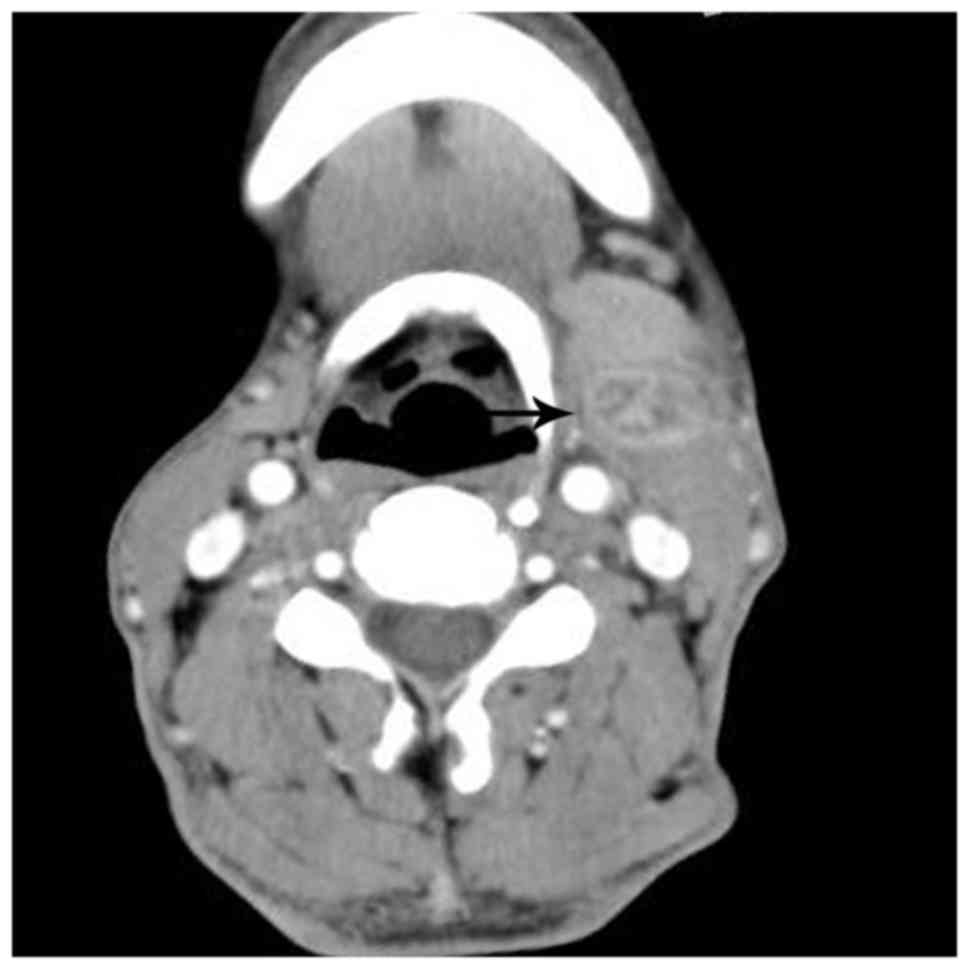

In total, there were 17 enlarged lymph nodes identified in 10 cases, of which 12 nodes were scanned on enhanced MRI, 3 on enhanced CT, and 2 on enhanced CT and MRI. Among them, 13 nodes were located at the elbow, 2 in the neck, 1 in the groin and 1 in the axilla. Multiple lesions were identified in 4 cases, and singular lesions in 6 patients. All the lesions were round, well-delineated nodes or nodules. The size of the enlarged lymph nodes ranged from 0.8–3.0 cm. On the CT scans, all the 5 nodes identified exhibited relatively inhomogeneous isodensity to muscle, with patchy or astral low density in the center. Following enhancement, 2 of the 5 nodes demonstrated marked heterogeneous enhancement, with no enhancement of the patchy low-density central areas, 1 of the 5 nodes displayed heterogeneous enhancement with progressive ‘spoke-wheel-like’ (defined as radiating enhancement from the center) enhancement of the patchy low-density area (Fig. 1), and the other 2 nodes demonstrated heterogeneous enhancement with peripheral flower ring reinforcement of the astral low-density area, also known as the ‘rose flower’ sign.

Figure 1.

Lymphadenopathy in a 57-year-old man with cat-scratch disease at the intermediate stage in the left neck. The node (arrow) displays heterogeneous enhancement with ‘spoke-wheel-like’ enhancement of the patchy low-density area on an enhanced computed tomography scan following intravenous contrast administration.